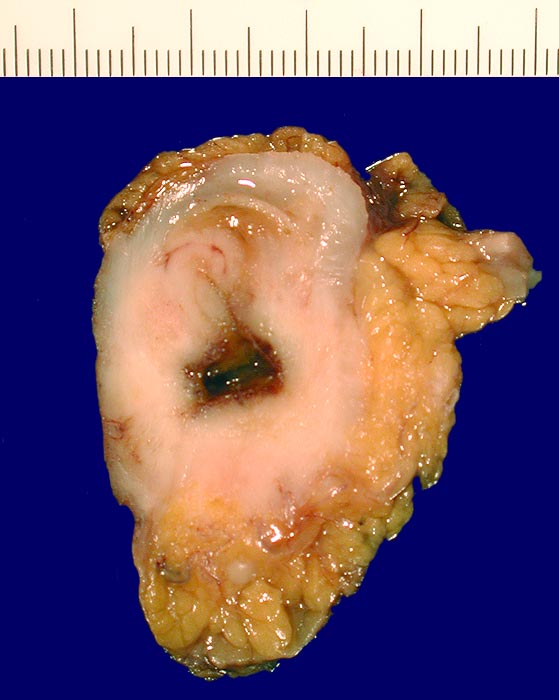

• Resektat sofort frisch und uneröffnet einsenden.

• Falls das Präparat eröffnet wird, Tumor vor dem Öffnen palpieren und Darm auf der gegenüberliegenden Seite eröffnen.

• Tiefen Weichgewebsresektionsrand mit Faden markieren.